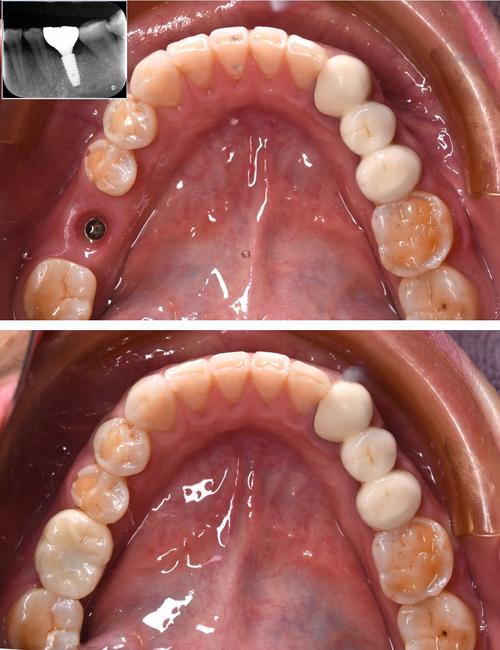

(图片来源网络,侵删) -